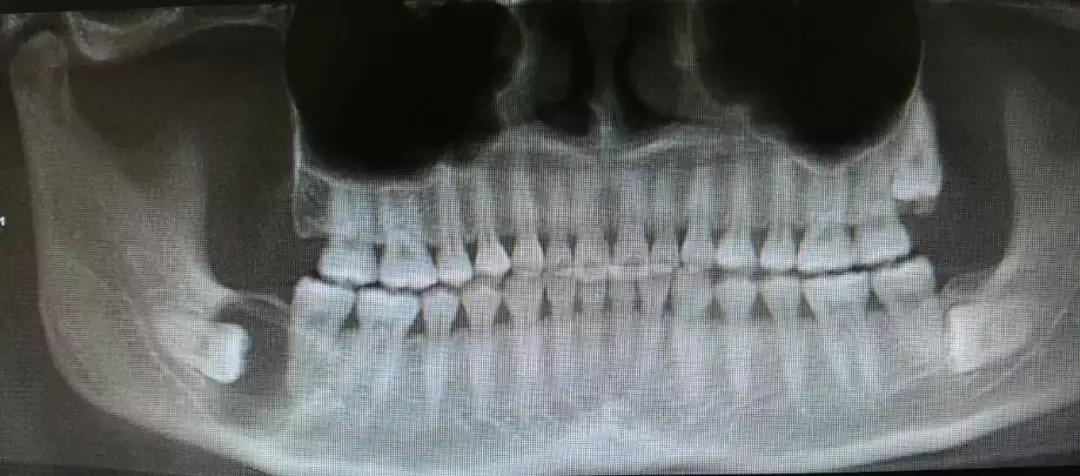

智齿阻生,萌出不全

会引起局部肿胀疼痛

不是持续的胀痛,是那种反反复复红肿,特别磨人↓

你想着,等完全长出来就去拔,这一等又是一年多。

真相是,它真的就到这为止了,就露个尖儿↓